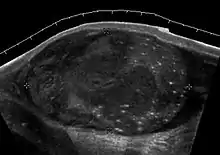

Teratoma Although teratoma is the second most common testicular tumor in children, it affects all age groups. Mature teratoma in children is often benign, but teratoma in adults, regardless of age, should be considered malignant. Teratomas are composed of all three germ cell layers, i.e. endoderm, mesoderm and ectoderm. At ultrasound, teratomas generally form well-circumscribed complex masses. Echogenic foci representing calcification, cartilage, immature bone and fibrosis are commonly seen [Fig. 5]. Cysts are also a common feature and depending on the contents of the cysts i.e. serous, mucoid or keratinous fluid, it may present as anechoic or complex structure [Fig. 6].